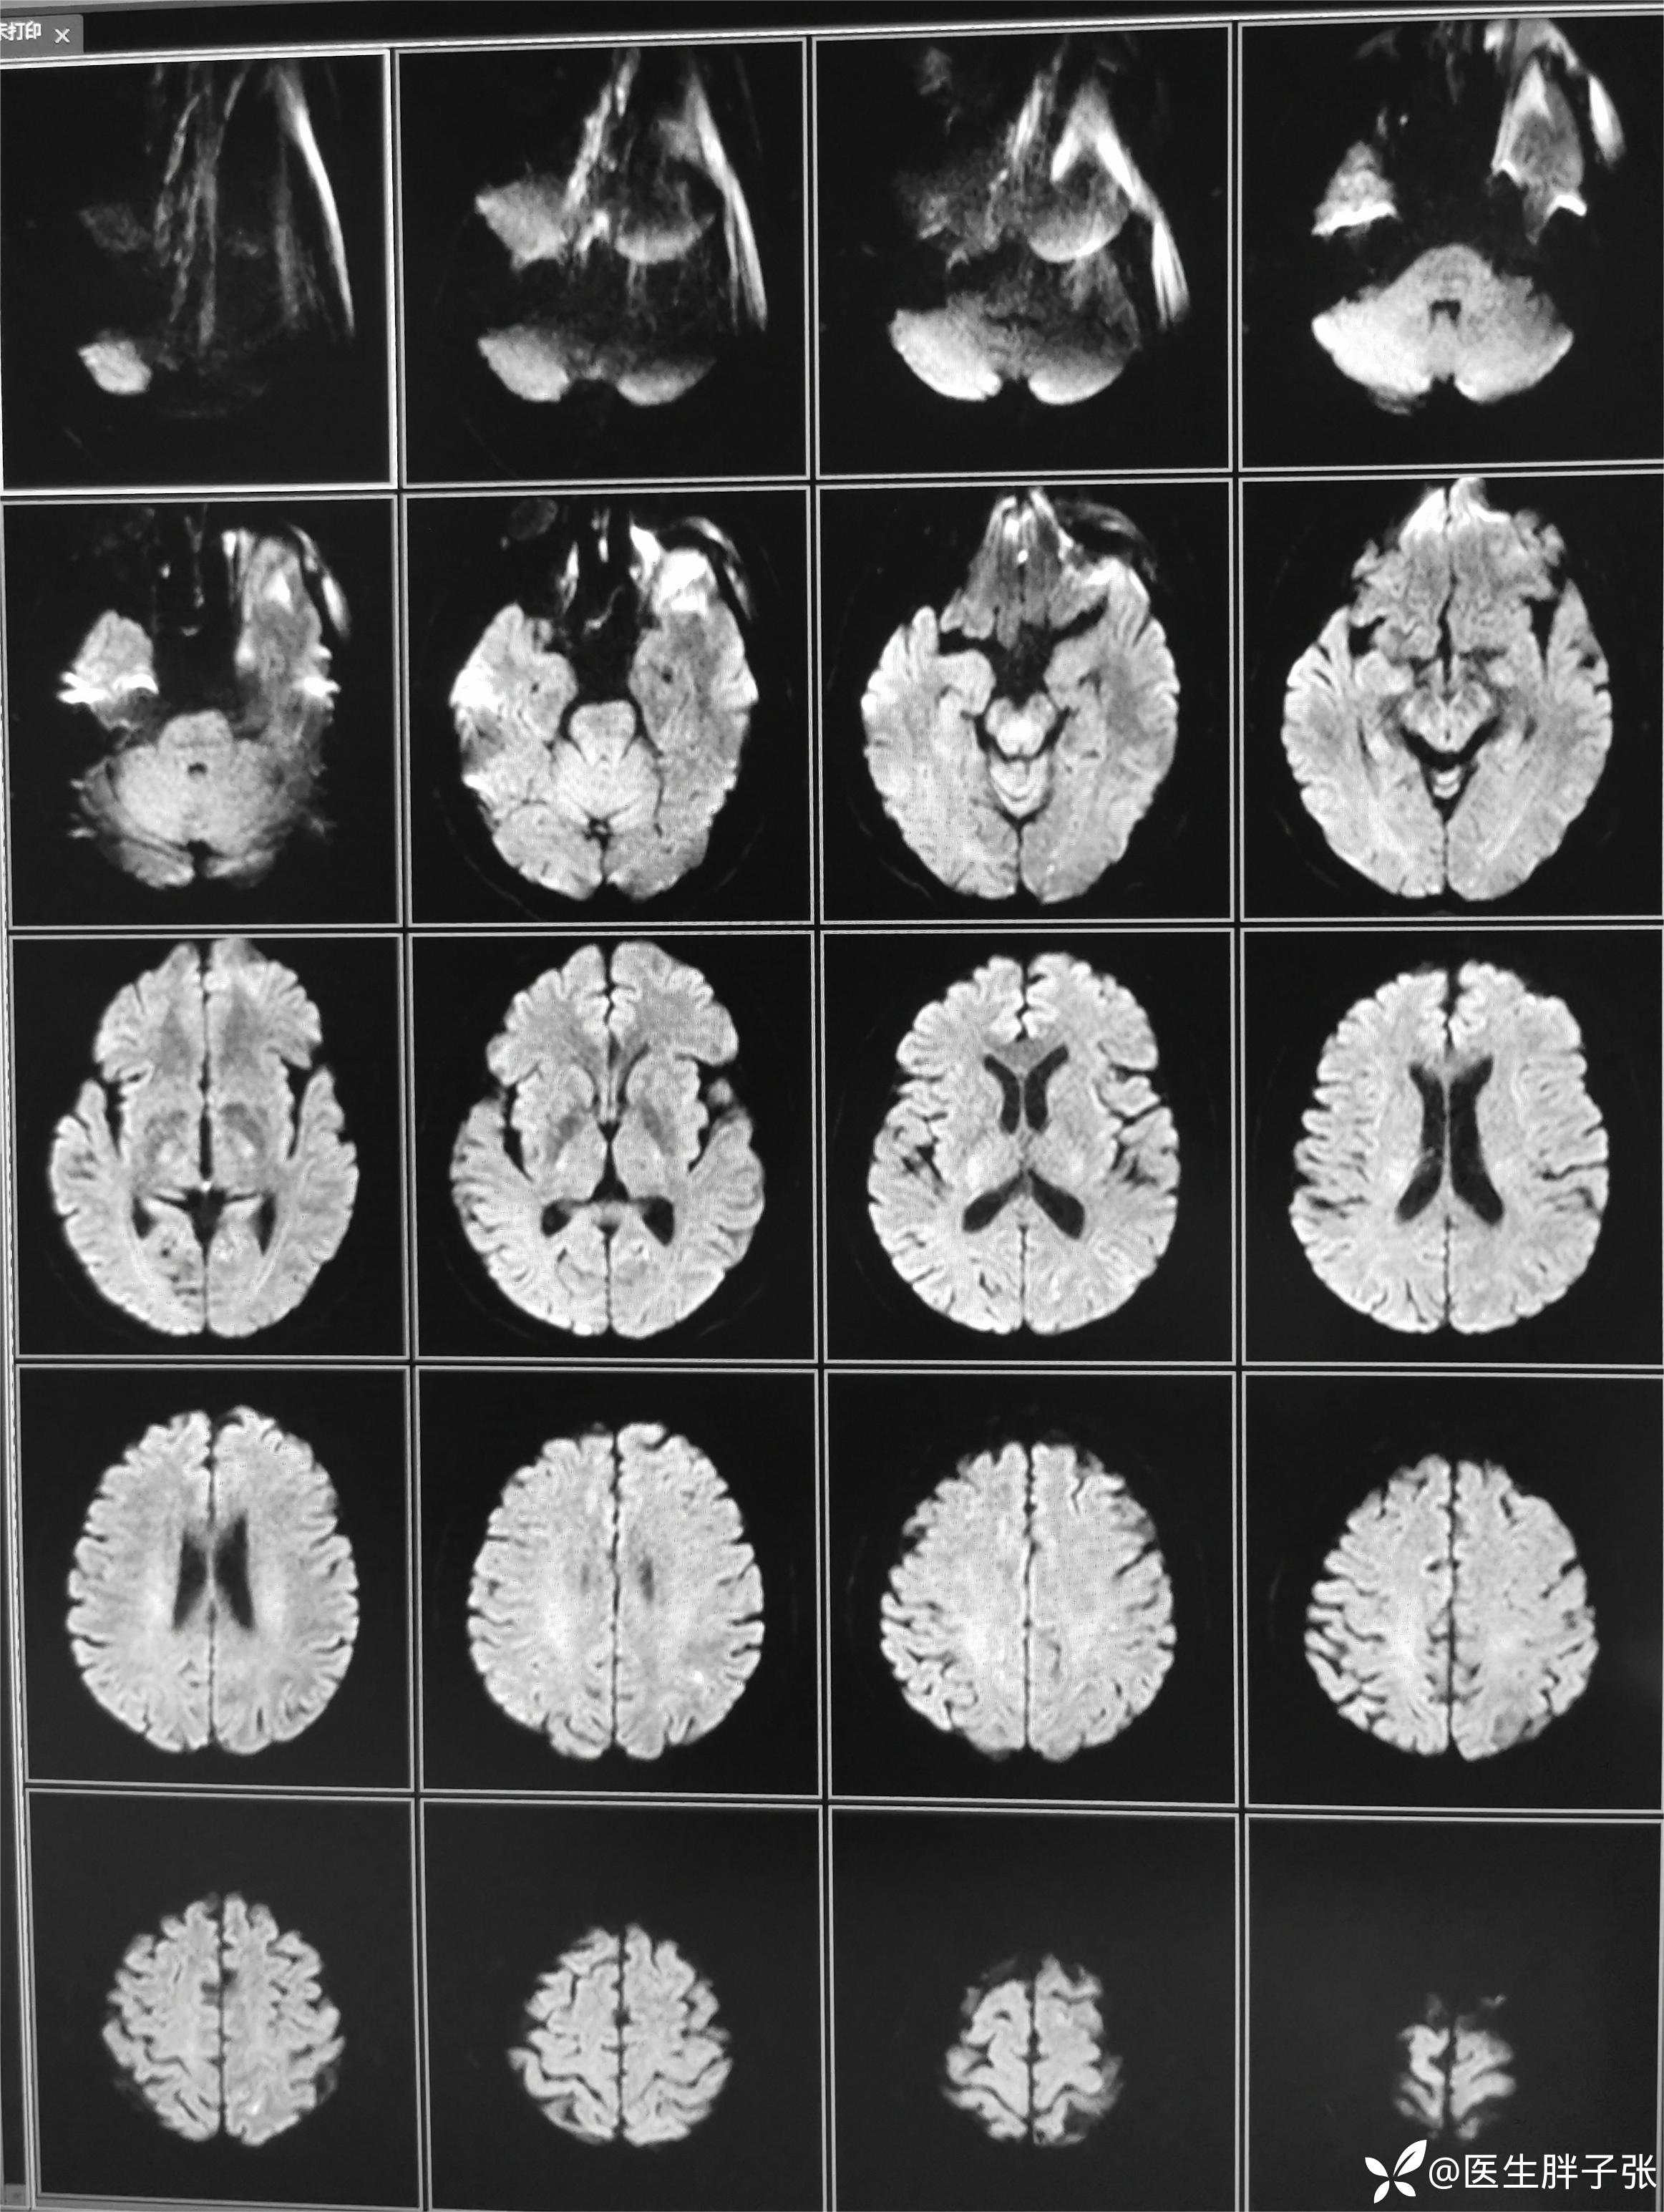

颅脑MR回报左侧顶叶新近梗死灶;多发腔隙性脑梗死及缺血灶;MRA未见异常。

再次查看核磁,考虑患者左侧顶枕叶及右侧枕叶脑组织存在混杂信号。

结合患者应用甘露醇后症状缓解,值班医生认为存在静脉窦血栓可能。